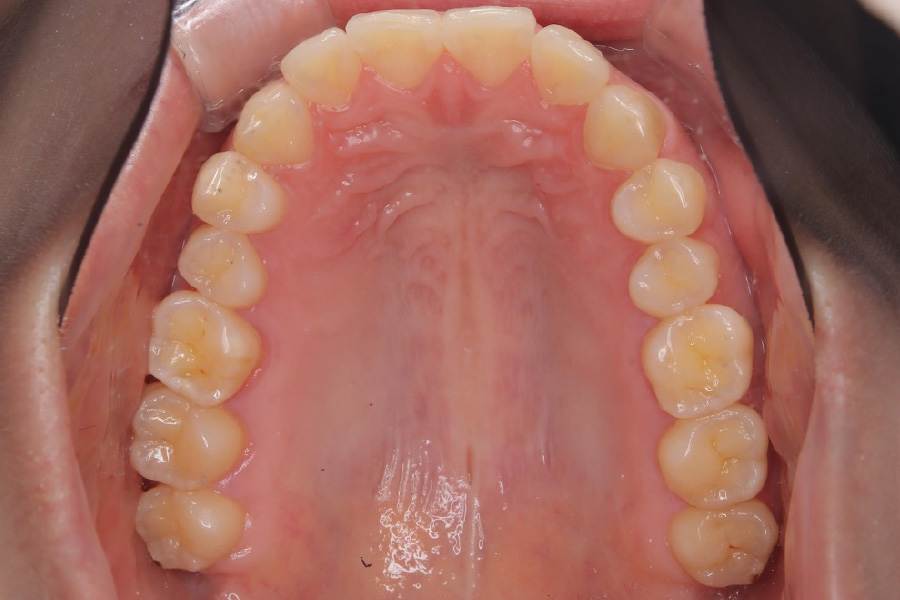

【20代女性】

歯のガタつきを

インビザライン矯正で治療したケース

治療前

主訴 ガタつき

期間 2年

費用 220,000円〜660,000円

治療内容 インビザライン矯正

非抜歯